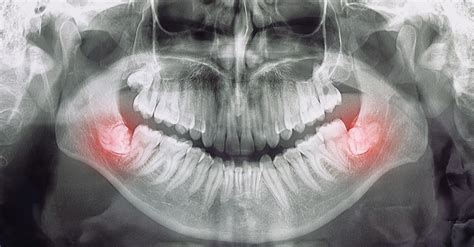

La necesidad de extraer las muelas del juicio surge cuando están impactadas, causan dolor persistente, infección, o cuando hay riesgo de daño a otros dientes. Cuando la muela del juicio empieza a molestar, es fundamental ir al propio odontólogo para que, gracias a un examen clínico y radiográfico, haga un correcto diagnóstico y plantee el eventual plan de tratamiento.

Las indicaciones para la extracción de dientes sintomáticos están recogidas en la tabla 1 y, por lo demás, no se pretende seguir insistiendo aquí sobre este tema. Un asunto más complejo es evaluar los beneficios y los riesgos de la extracción quirúrgica profiláctica para evitar posibles patologías asociadas a los terceros molares (fig. 1). Entre los argumentos a favor se encuentran evitar eventuales pérdidas de jornadas laborales y mejorar la calidad de vida.